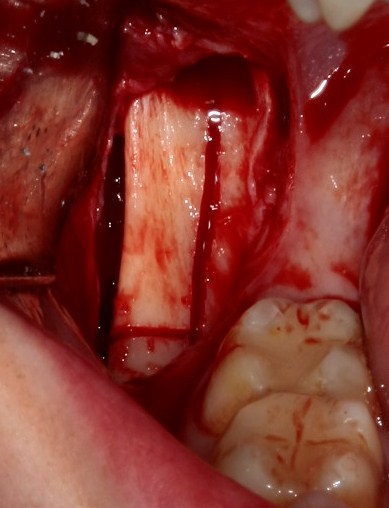

Простой. Надежный. Дешевый. Способ остеопластики.